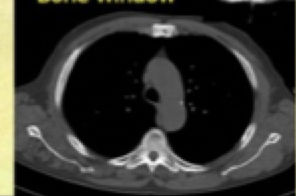

9

Q

terms for anatomic definition

A

-Chest CT scans are usually “windowed” and displayed in at least 2 FORMATS*

-ex. if looking for pleural effusion -> look for lung window -> changes gray scale so you can see it better

-bone window- fracture

-Windowing AKA “grey-level mapping”: contrast enhancement.

-process in which the CT image greyscale component of an image is manipulated to highlight particular structures.

14

What are all the windows

BLM BSA:

Bone

lung

mediastinum

brain

soft tissue

abdomen

Windowing = grey-level mapping contrast enhancement

- adjusts the display settings of the CT images to emphasize specific types of tissue, making it easier to diagnose various conditions